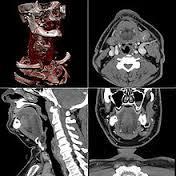

下面就是CT。X线的扫描等于把人体压成一张薄薄的纸来观察,但是只有一个方向,CT就是把人切成一个个薄片,相当于多层的X线扫描。可以把人切成1cm 的薄片,也可以切成0.5cm。越薄精确度就越大。再举个简单的例子,人体的肿瘤就像在馒头里藏了一颗沙子。X线可以看穿馒头,发现沙子,但是仅仅是平面效果。也就是仅仅在一个平面上,只知道在馒头中间有沙子,并不知道在馒头里面多深的位置。这时候就需要CT,比如说0.5cm的扫描,就相当于把馒头间隔0.5cm切片,把每一片拿出来找这颗沙子。这时候,稍微大点的沙子都可以被发现。而且可以确定在多深的位置。但是如果是更小的沙子就,刚好在0.5cm的两层之间,也可能不会被发现。

这就是我们说检查的敏感性问题。当然扫的层面越多,敏感性就越高,但是事实并没有那么简单。第一,仪器的分辨率要求高,价格也就相对更高;第二,扫描的层面越多,时间越长,患者受到的辐射也就越大。目前CT的分辨率对于一般的疾病都可以检查,适用范围也较广。CT扫描的时间也相对较短,根据扫描位置的不同,几十秒或者几分钟基本上都可以完成。当然X线更快,就是“咔”的一下。

磁共振和CT的区别主要在于成像的性质,CT是根据组织的密度,由于人体不同组织的密度不同,来发现病灶;而磁共振是判断不同加权所产生的不同信号。磁共振于对软组织滑膜、血管、神经、肌肉、肌腱、韧带、和透明软骨的分辨率高。由于其特殊的性质,磁共振看骨头不行,而在大脑的检查中则有着不可替代的作用。